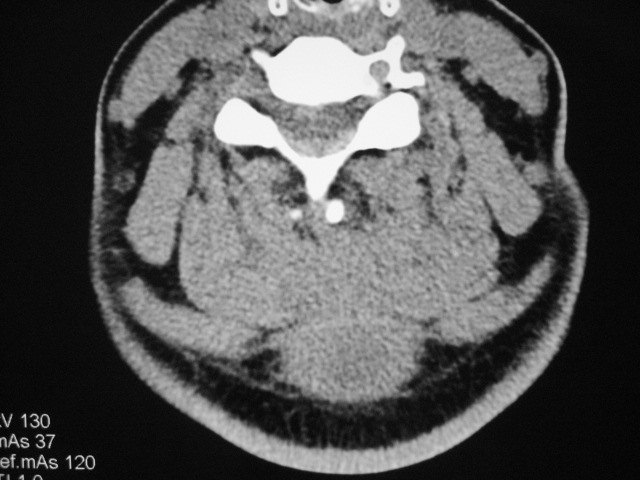

女,46岁,发现颈后区肿块3月余.

颈后软组织肿块,内可见坏死区及点状钙化,邻近颈椎棘突可见破坏,邻近肌间隙模糊,肿块周围脂肪间隙可见索条状影。

考虑:1)感染,结核可能;

2)肿瘤不能排除。